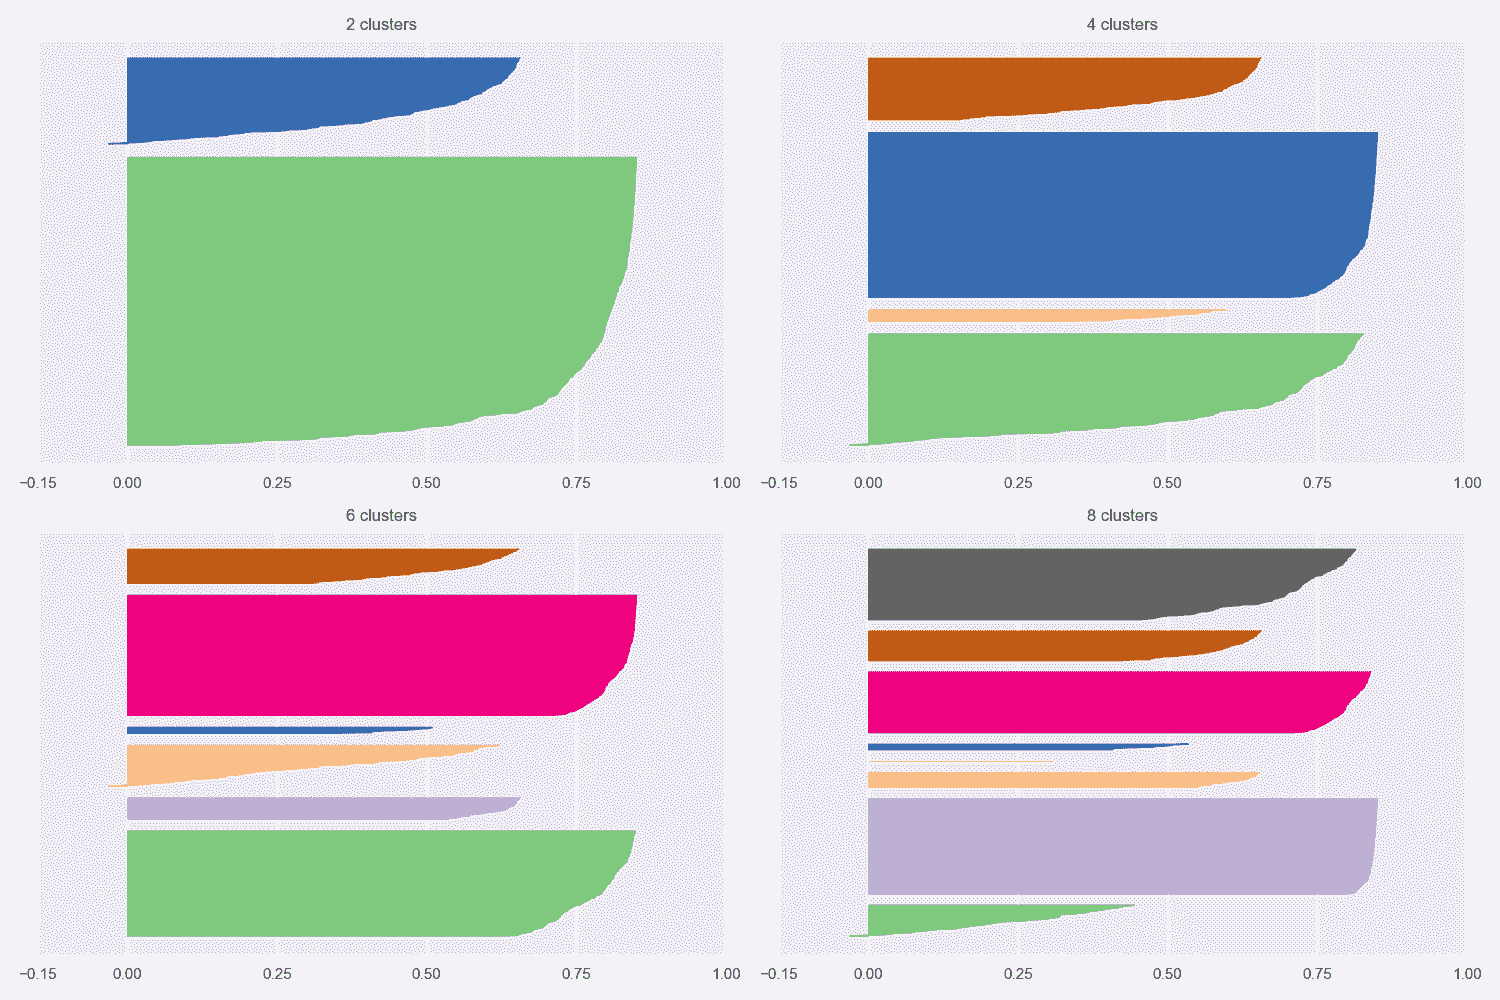

让我们考虑K = {2, 4, 6, 8}的乳腺癌威斯康星州数据集的轮廓图(完整代码包含在存储库中):

乳腺癌威斯康星州数据集的轮廓图

第一张图显示了K = 2的自然聚类。 第一个轮廓非常清晰,表明平均群集间距离具有较大的差异。 而且,一个集群比另一个集群具有更多的分配(即使它不那么尖锐)。 从数据集描述中,我们知道这两个类别是不平衡的(357 良性与 212 恶性),因此,不对称是部分合理的。 但是,一般而言,当数据集平衡时,良好的轮廓图的特征是具有均匀轮廓的均质群集,其圆形轮廓应接近 1.0。 实际上,当形状类似于长雪茄时,这意味着群集内距离非常接近其平均值(高内聚),并且相邻群集之间存在明显的分隔。 对于K = 2,我们拥有合理的分数,因为第一个群集达到 0.6,而第二个群集具有约 0.8 的峰值。 但是,尽管后者的大多数样本的特征是s(•) > 0.75,但在前一种样本中,约有一半的样本低于 0.5。 分析表明,较大的聚类更均匀,并且 K 均值更易于分配样本(即,就度量而言,x[i] ∈ K[2]的方差较小,在高维空间中,代表K[2]的球比代表K[1]的球更均匀。)。

其他图显示了类似的情况,因为已检测到非常紧密的聚类以及一些尖锐的聚类。 这意味着宽度差异非常一致。 但是,随着K的增加,由于分配的样本数趋于变得相似,因此我们获得了更加均一的群集。 具有s(·) > 0.75的非常圆形(几乎矩形)的群集的存在证实了数据集至少包含一组非常有凝聚力的样本,相对于分配给其他群集的任何其他点的距离都非常接近。 我们知道,恶性类(即使其基数更大)更为紧凑,而良性类则分布在更宽的子空间中。 因此,我们可以假设,对于所有K来说,最圆的群集是由恶性样本组成的,而其他所有群集都可以根据其清晰度进行区分。 例如,对于K = 8,第三群集很可能对应于第一图中第二群集的中心部分,而较小的群集包含属于良性子集的孤立区域的样本。

如果我们不了解基本事实,则应同时考虑K = 2和K = 8(甚至更大)。 实际上,在第一种情况下,我们可能会丢失许多细粒度的信息,但是我们正在确定一个强大的细分领域(假设由于问题的性质,一个集群的凝聚力不是很高)。 另一方面,在K > 8的情况下,群集明显更小,具有适度的内聚性,它们代表具有某些共同特征的亚组。 正如我们在上一节中讨论的那样,最终的选择取决于许多因素,这些工具只能提供一般的指示。 此外,当聚类是非凸的或它们的方差未在所有特征之间均匀分布时,K 均值将始终产生次优表现,因为所得聚类将包含较大的空白空间。 如果没有特定的方向,则群集的最佳数量与包含均匀(宽度大致相同)的圆形图的图相关联。 如果形状对于任何K值仍然保持清晰,则意味着几何形状与对称度量不完全兼容(例如,群集非常拉伸),应考虑其他方法。